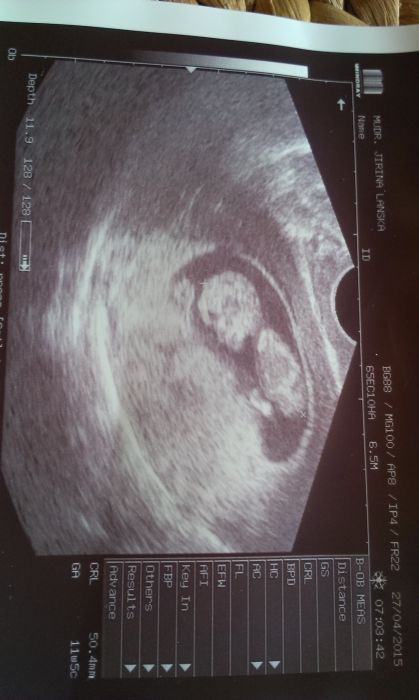

Zdravím vsechny,mám po kontrole.Krev ok,mimi 5,4cm,dle kalkulacky 11+1,dle ult.11+5.Pěkně sebou smykalo:-D..Taky mi je stále zle,ale asi si taktéž,zvykam..přijde mi,že to bylo horší..;-)..Krev.skupina O+..

ivyy krásný mimísek :) Jak se pěkně natočil z profilu. Mě dneska Dr málem fotku neudělal, protože sebou mimi škubalo, rejdilo, pořád se k nám otáčelo zády :D Bylo úplně hyperaktivní :D Tak si říkám - doufám že až povyroste, tak se trošku zklidní, nebo budu vypadat že se mi tam klube vetřelec :D

Peti děkuji, fotecky byly dvě,ale dr.si jednu nechává,tam bylo dokonce natočené obličejem,ale i tak je hezký videt.Docela jsem cucela,jak se zmenilo a vyrostlo za dva týdny,ale to jsem v šoku zatím vždy-pozitivně,a vždy se moc těším..Teď zrovna 4.5.na screening,snad bude vše ok jako doposud:-)..Taky bylo dnes nějaké hyper..;-)Neudržela jsem se,mám první dvě bodycka..neutrální..s zirafkama..:-P

Tak to já jsem zatím asi jediná co ma v břichu lenosku. Srdíčko ji tluklo o sto šest ale pohyb zadnej. Jinak holky moc gratuluju. Ivyy krásna fotka. Me nevolnosti taky nepresly, ikdyz sem myslela ze už jo včera jsem si to vynahradila ;)

:-D Kacabo,určitě to nebude lenousek:-D,minule se mi naše miminko zdálo poněkud ,,kulatoucke,,a líné,jakoby ,,sedělo,,jediný pohyb byl ten srdeční,dr.mě uklidnila,že asi spí,hlavní je prej tlukot srdce;-). .za to dnes se mlelo o sto šest:-P..k nevolnostem..nejsou tak časté,za to intenzívnější a delsi pobyt na wc ráno,či večer..koupila jsem si Gaviscon,je supr na prekyseleni.